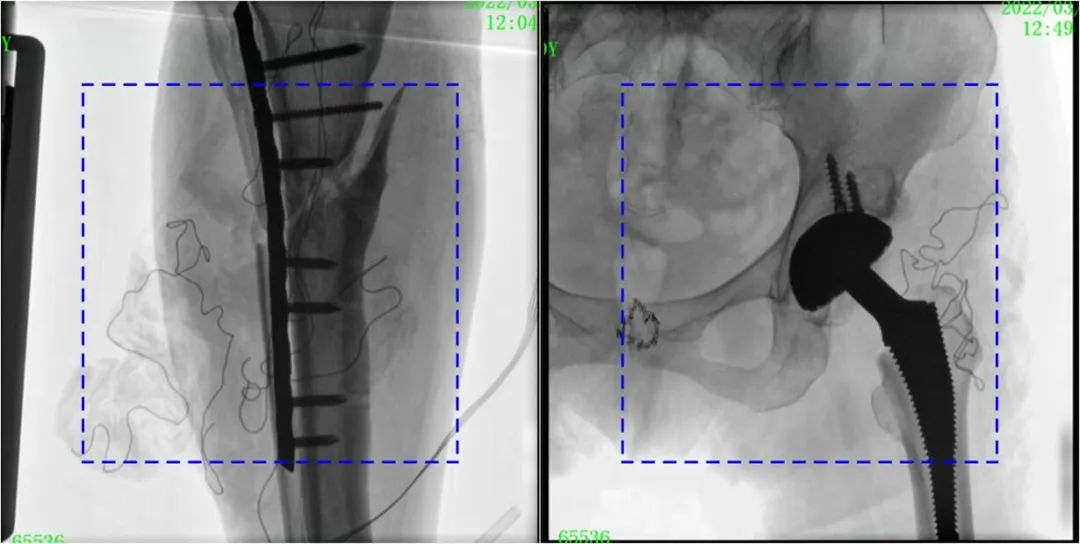

與傳統的21CM×21CM成像尺寸相比,普愛(ài)醫療大平板一體式C形臂具有30CM×30CM更大成像尺寸,能夠一次成像5.5節椎體,呈現更全面的影像信息,即便是手術(shù)經(jīng)驗不豐富的年輕醫生也能通過(guò)圖像迅速判斷椎體節段、定位手術(shù)部位,避免因為視野不足而造成的多次定位、反復曝光,提高效率的同時(shí)避免過(guò)量攝入輻射。

普愛(ài)醫療大平板一體式C形臂圖像與傳統圖像對比(藍色虛線(xiàn)內為傳統21CM×21CM平板的成像區域)